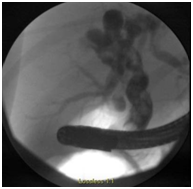

An 11-year-old girl with history of sickle cell trait and allergic rhinitis presented to the emergency department for pruritus. She had been evaluated at an urgent care clinic three weeks prior for generalized rash and pruritus, and was diagnosed with contact dermatitis. At current presentation, rash had resolved but she had persistent pruritus. No abdominal pain. She had scleral icterus, but family reported this was not uncommon as it occurred for over a year and seemed to get worse with her “seasonal allergies”. Initial assessment showed a thin nontoxic appearing girl with normal vital signs and an exam significant for icteric sclerae, excoriations but no rash, and a nontender abdomen with liver palpable 2cm below the right costal margin. Laboratory results showed elevations in direct bilirubin, alkaline phosphatase, and GGT. Ultrasound showed intrahepatic biliary dilation with an echogenic area in the common hepatic duct suggestive of sludge. She had a magnetic resonance cholangiopancreatography (MRCP) that showed diffuse dilation of the intrahepatic, common hepatic, and common bile ducts; a distended gallbladder; and a T2 hypodense lesion in common bile duct extending into common hepatic duct that was consistent with biliary sludge (Figure 1), with suspicion for choledochal cyst. She then had an upper endoscopy, which was significant for a lesion protruding from the ampulla that had the appearance of a blood clot. It was extracted after sphincterotomy, and noted to have a thin stalk-like attachment, measuring 1.3cm in length, which was partially resected and sent to pathology (Figure 2&3). Pathology was significant for a polypoid tumor with variable cellularity, and “tadpole” shaped cells having cytoplasmic cross striations, and a high proliferative index by Ki67 stain. These findings were diagnostic of a botryoid variant of embryonal rhabdomyosarcoma. She was started on chemotherapy with vincristine, adriamycin, and cyclophosphamide (VAC), and improved with this regimen. She has not required surgery or radiation (Figure 4A-4C).

Figure 4A Polypoid tumor with variable cellularity and vessels, HE, x40.

Figure 4B Tumor cells are “tadpole” shaped, HE, x200.

Figure 4C Tumor cells with cytoplasmic cross striations, HE, x400.